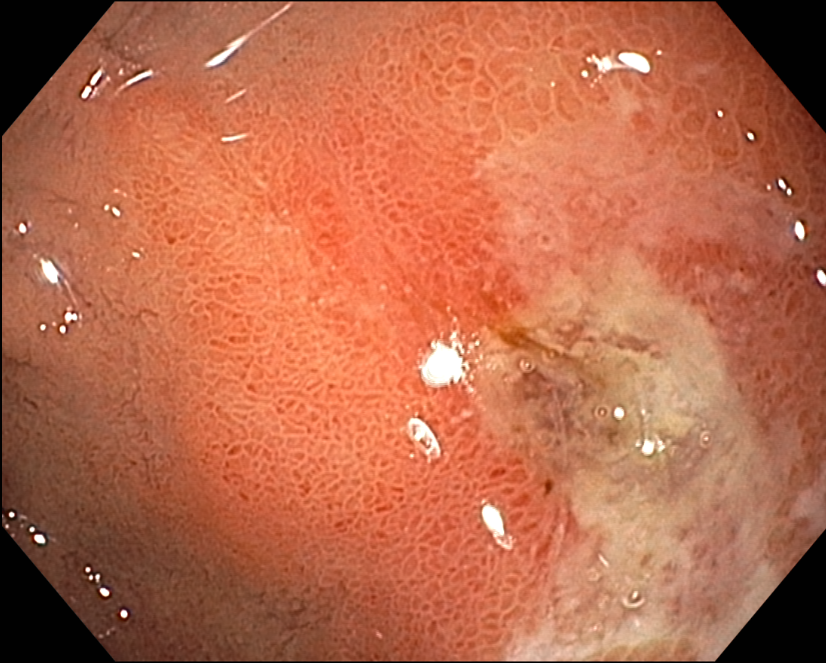

Duodenal ulcer, CLOtest : positive, biopsy proven H. pylori (+++)

PPI 치료 후 위내시경과 CLOtest : negative